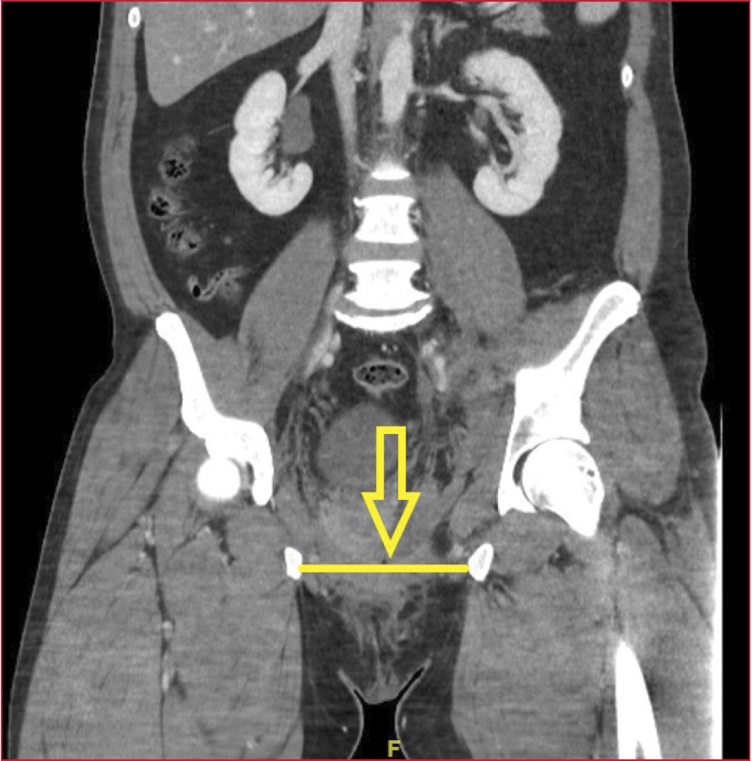

Hombre de 43 años, sin antecedentes personales de interés, que ingresa en nuestra Unidad, tras sufrir un traumatismo pélvico repetitivo con el cuerno o la perilla de la montura en la doma de caballo. El paciente es trasladado al Servicio de Urgencias hospitalario con incapacidad para deambular y dolor intenso. Se realiza una tomografía computarizada abdomino-pélvica de urgencia, que muestra una fractura inestable de pelvis tipo C2 de la clasificación de Tile, en libro abierto, con diástasis de la sínfisis púbica de 9,5 cm (Figura 1, flecha), articulación sacroilíaca izquierda y derecha (Figura 2, flechas), asociada con hematoma de partes blandas en el pubis y la región ilíaca izquierda, y sangrado activo en dicha zona. Se procede a la fijación externa urgente a cargo del equipo de guardia de Traumatología y se lo traslada a la Unidad de Cuidados Intensivos, donde posteriormente es sometido a fijación y osteosíntesis del anillo pélvico (Figura 3, flecha).

Figura 1. Tomografía computarizada de pelvis, corte coronal. Diástasis de la sínfisis púbica de 9,5 cm.